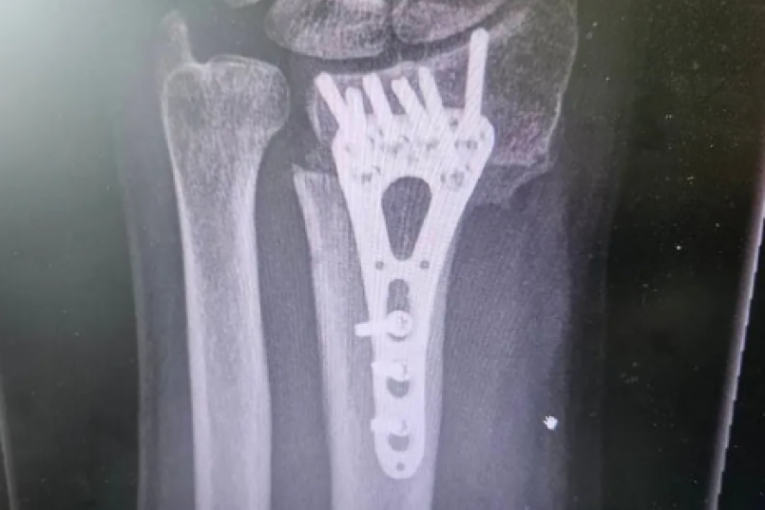

Voditelj Aleksandar Stanković podelio je fotografiju jezive povrede zbog koje je hitno operisan. Naime, Stanković je objavio uznemirujuću fotografiju iskrivljene ruke, zbog koje je morao da se podvrgne operaciji.

Strašna povreda dogodila se pre tri meseca, a on je sada pokazao kako je izgledao proces oporavka.

- Ovako je to izgledalo prije 3 meseca, a danas je sve u redu. Slomio sam ruku (prva fotka) i operisali su me u Opštoj bolnici Sisak na čelu s doktorom Abelom Balaškom. Ruka je zacelila i hvala im što su svoj posao odradili profesionalno i s ljubavlju! - napisao je.